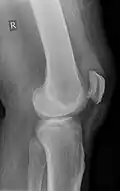

Quadriceps tendon rupture in plain X-ray -